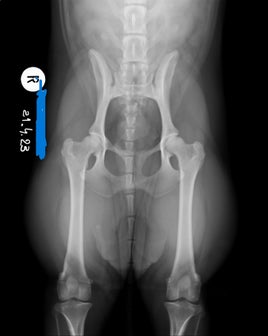

Noudatan Pevisaa sekä rodun geenitestejä. Myös luusto kuvataan (LTV, VA, SP, kyynärät ja lonkat).